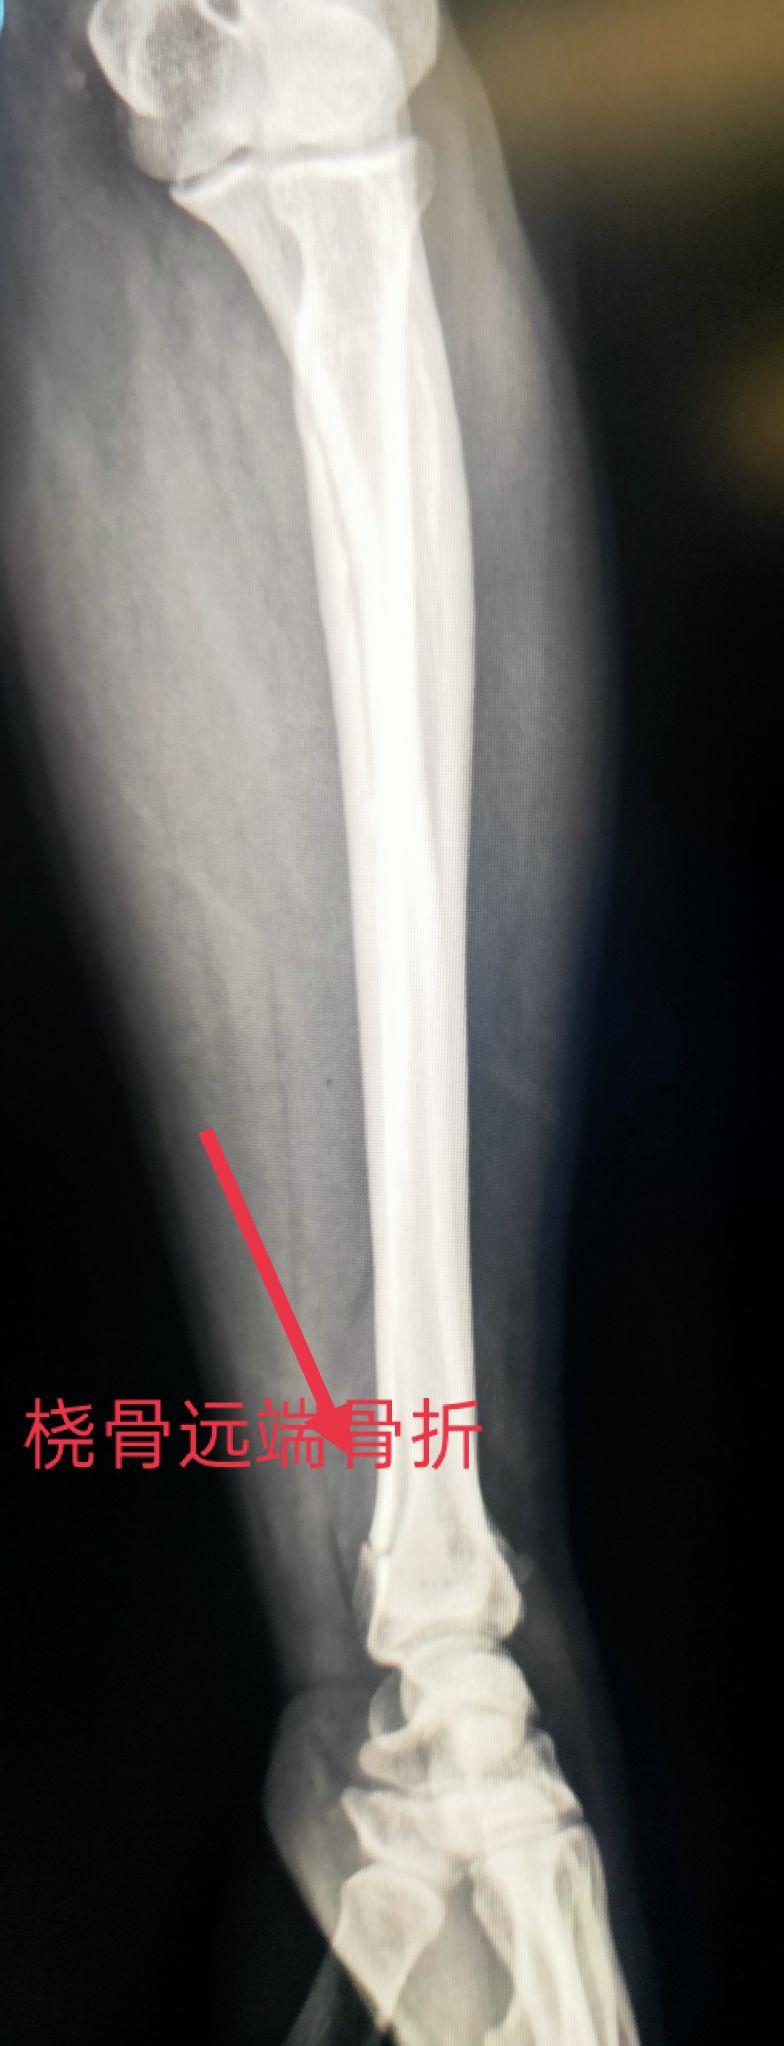

四、尺、桡骨骨折X线片

尺骨桡骨骨折以桡骨远端骨折多见。其次是尺骨桡骨双骨折,多发生于青少年。